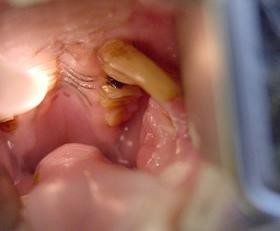

Choroby zebów u królikaW przychodni lekarz obejrzy najpierw głowę i szczękę , siekacze i zgryz można łatwo sprawdzić podnosząc wargi królika. Specjalnym oświetlonym otoskopem (z metalowa końcówką), można ocenić zęby przedtrzonowe oraz miękkie części np. język, policzki. Przy najmniejszym podejrzeniu anomalii cała jama gębowa powinna zostać dokładnie przebadana. Z powodu dużego zagrożenia urazami podczas badania, powinno być one przeprowadzone pod narkoza. Choroby zebów u królika Tylko podczas znieczulenia ogólnego można przeprowadzić szczegółowe badanie wszystkich miejsc w szczęce. Zdjęcie rentgenowskie przy zamkniętej i otwartej szczęce , pozwoli wykryć szczękowo-ortopedyczne problemy. Poza tym można zobaczyć przerost zębów, czy zmian kości i korzeni spowodowanych ropniem.

Choroby zebów u królikaGłównym celem jest przywrócenie prawidłowego zgryzu siekaczy i zębów trzonowych, tak żeby umożliwić naturalne gryzienie i żucie. Skracanie siekaczy małym zwierzętom domowym jest z reguły możliwe bez użycia narkozy. Aby uniknąć powstawania odłamków/ rys np. aż do korzenia zrezygnujmy z cążek. Do tego lepiej nadają się szybko obracające się wiertła z diamentowa tarcza. Stopień skracania zależy od rodzaju zwierzęcia. U królików siekacze w przeciwieństwie do trzonowych dotykają się ze sobą, dobranie prawidłowej długości nie stanowi problemu. U gryzoni na odwrót. Zęby trzonowe, przy zamkniętej szczęce, dotykają się natomiast siekacze nie maja ze sobą kontaktu. Profesjonalne skracanie zębów trzonowych jest możliwe tylko pod narkoza czy znieczuleniu ogólnym. Choroby zebów u królikaTylko w ten sposób można dokładnie zbadać jamę ustna i po wykonaniu zdjęcia RTG rozpocząć prawidłowe, a dla pacjenta bezpieczne leczenie. Przy zachowaniu dużej ostrożności i ochronie miękkich części, szybko obracającym się instrumentem przeprowadza się korekcje zgryzu. Zdjęcia pokazują zęby przed i po operacji. Nie powinno się do tego celu używać cążków, ani pilników diamentowych, ponieważ ryzyko naruszenia fraktury zęba, czy skaleczenia miękkich części jamy gębowej jest nie do przewidzenia. Podczas przywracania naturalnego zgryzu zwierzakowi, należy pamiętać że powierzchnia gryząca powinna być odchylona o 10°, u świnek morskich o30 ° , a u szynszyli jest prawie horyzontalna. Jeśli nie można uniknąć usunięcia zęba,powinno się po udanej ekstrakcji oczyścić także zębodół. aby zapobiec odrostowi tkanki zęba. W związku z ograniczeniem jakim jest mały otwór gębowy zwierząt, czasami dojście do zęba jest łatwiejsze od zewnętrznej strony. Po usunięciu zęba , ząb przeciwległy ma tendencje do nadmiernego rozrostu, to może doprowadzić do wrośnięcia zęba w puste miejsce. Regularne kontrole i korektura jest nieodzowna.